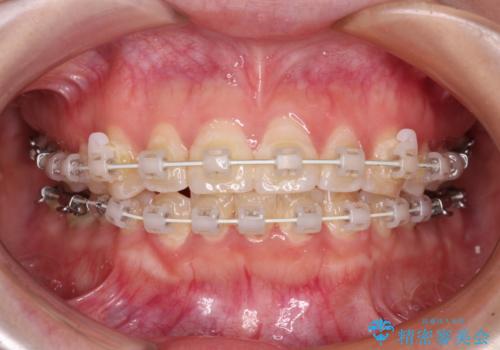

- 矯正装置

- 審美装置

患者様も驚く、僅か10か月での治療終了となりました。